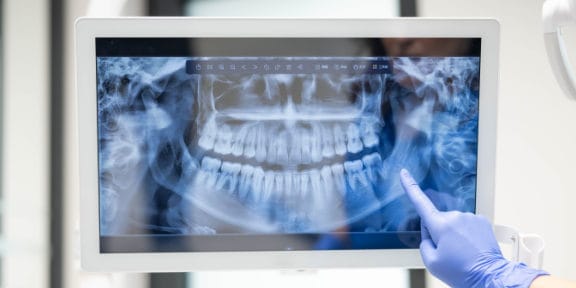

Digital Panoramic X-Rays

Panoramic x-rays offer patients a complete detailed image of the entire mouth including the teeth, jaw (upper and lower), sinuses, and TMJ.

It provides a complete picture on how everything looks and relates to each other.

Panoramic X-Rays

Panoramic x-rays offer patients a complete detailed image of the entire mouth including the teeth, upper and lower jaws, sinuses and TMJ.